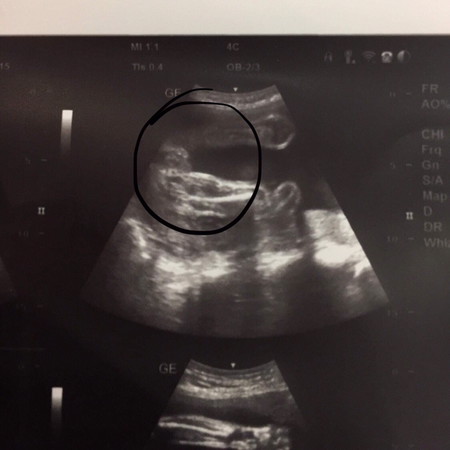

ลูกสาวใช่ไหมค่ะ

แบบนี้ได้ลูกสาวใช่ไหมค่ะ ?

แล้วเเบบนี้ชายรึหญิงค่ะ

ดีใจด้วยค่ะ ลูกสาวน๊า

ชายใช่ไหมค่ะ

ลูกสาวค่าา ☺️

ลูกสาวววว

ลูกสาวคร่า

สาวน้อยค่ะ

ลูกสาวจ้าแม่